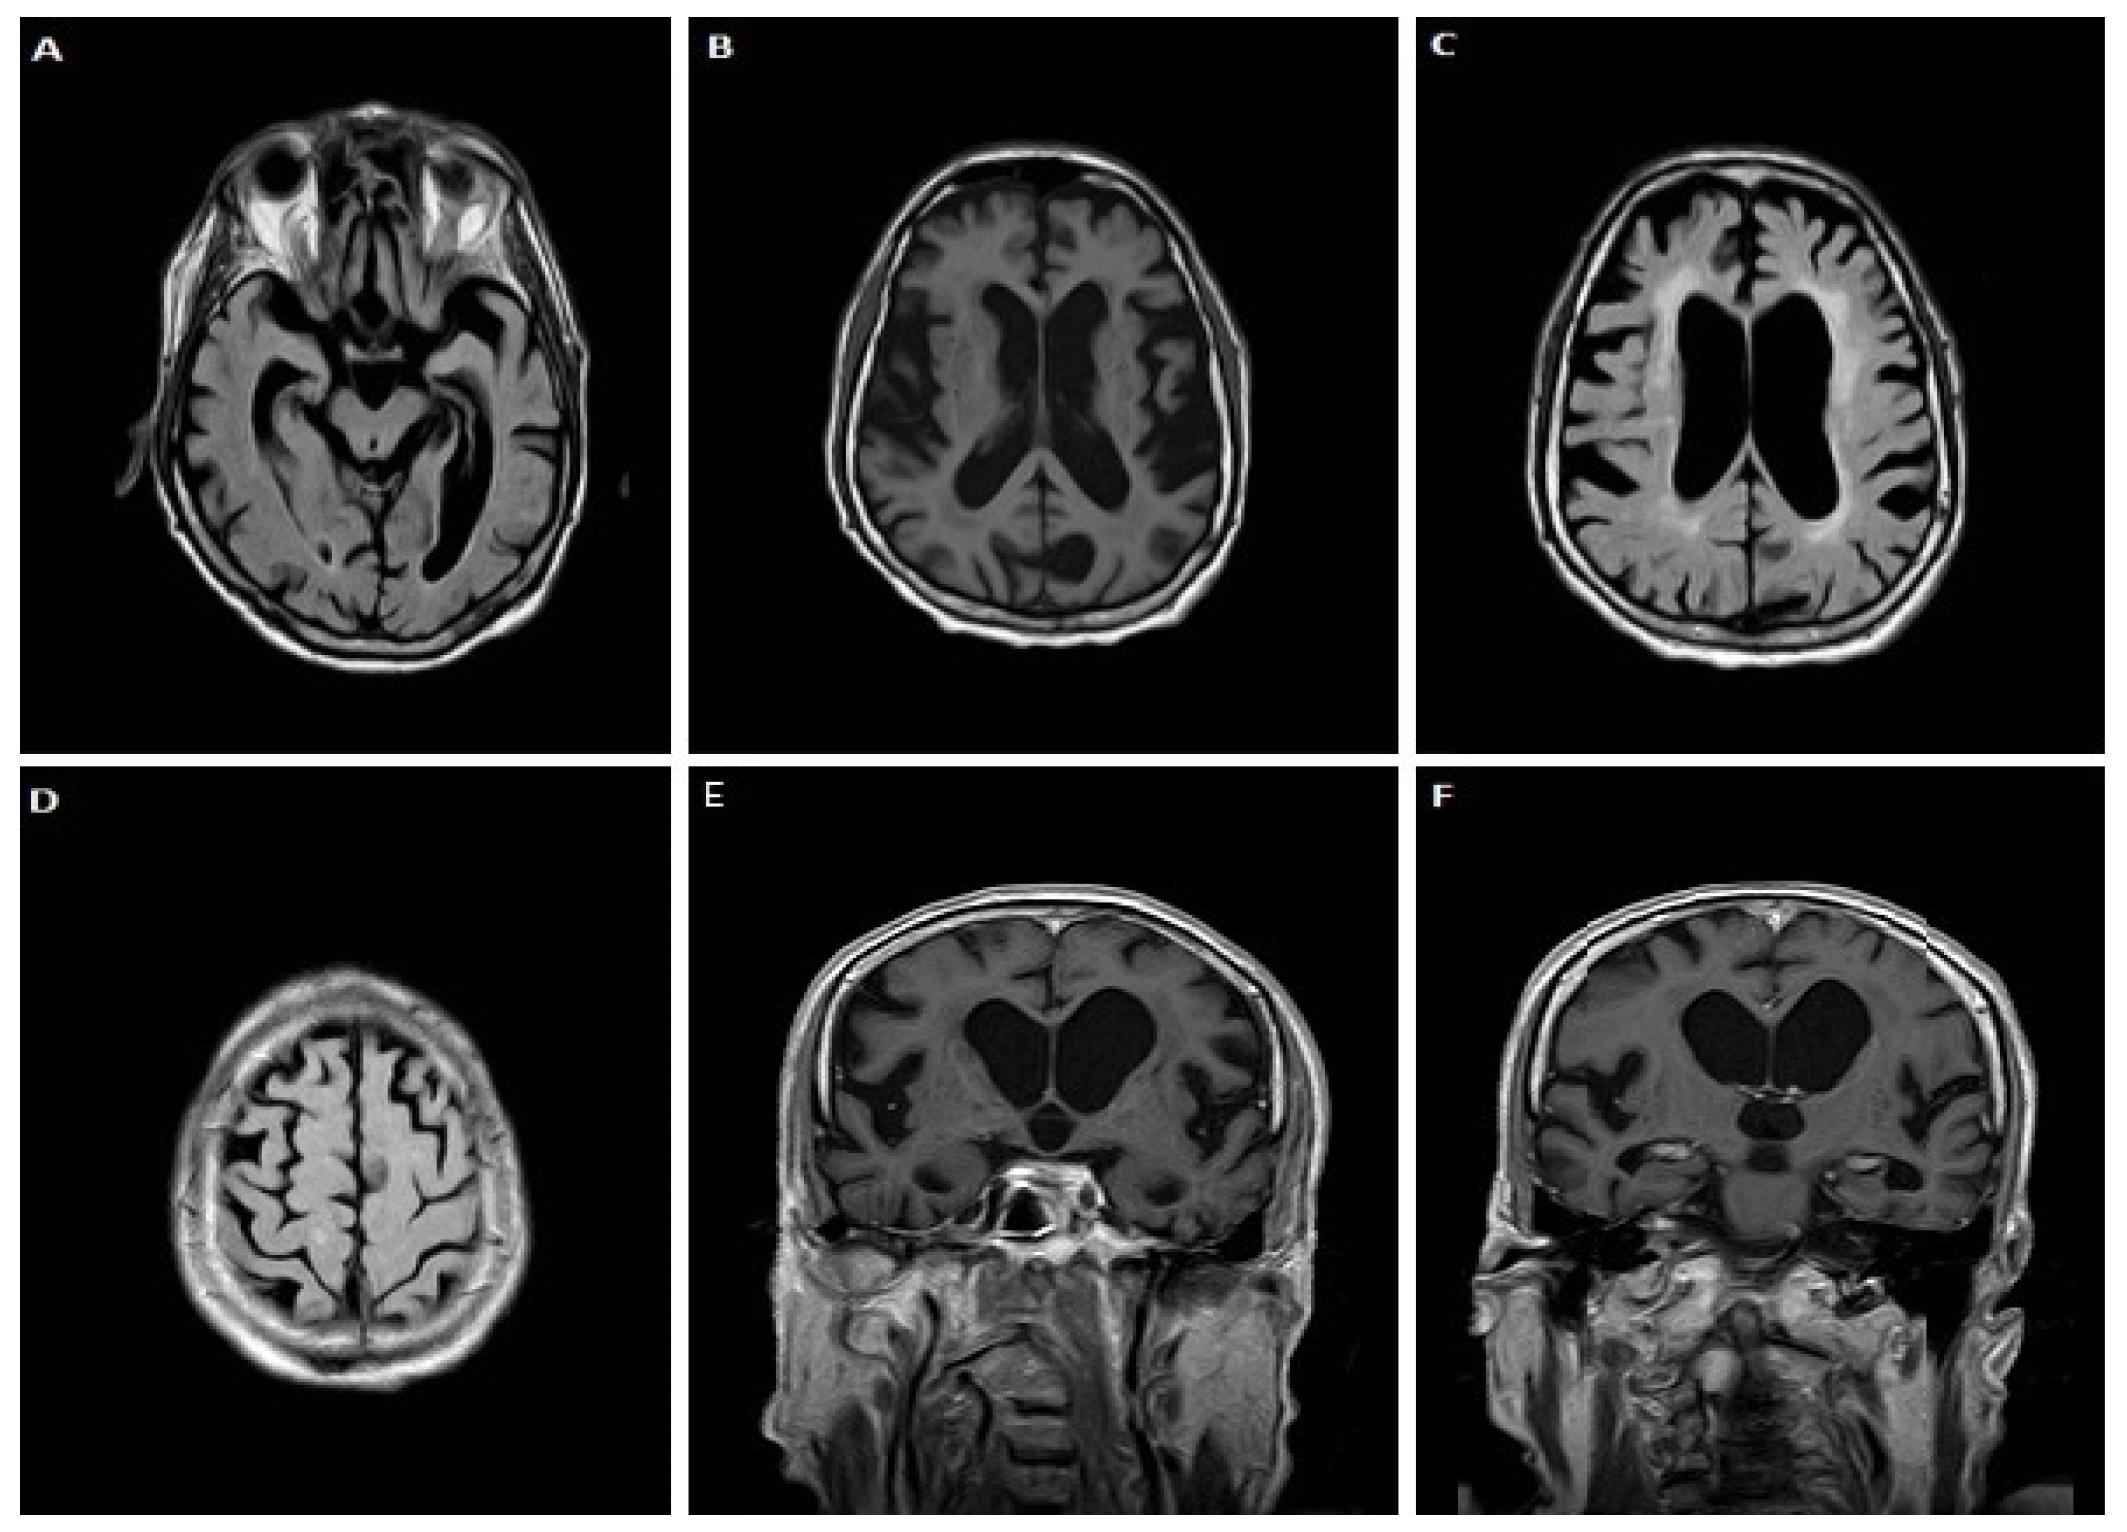

3.1.3. Case 3